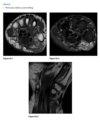

23 year old man with pain in the right hip

An anteroposterior view of the pelvis

shows flaring of the metaphyseal regions of

the proximal femurs and numerous osteochondromas

arising from the right iliac crest, pubic bones, and proximal right femur (arrows).

Axial CT through upper pelvis - Large right exostosis with soft tissue mass.

AP radiograph of knee - multiple osteochondromas arising from femur and fibula.

DIAGNOSIS: Multiple hereditary exostosis

AD disorder age 10-20s

Signs of malignant transformation - Growth of previous stable exostosis, new or increasing calcifications, new bony erosion

Associated with chondrosarcoma